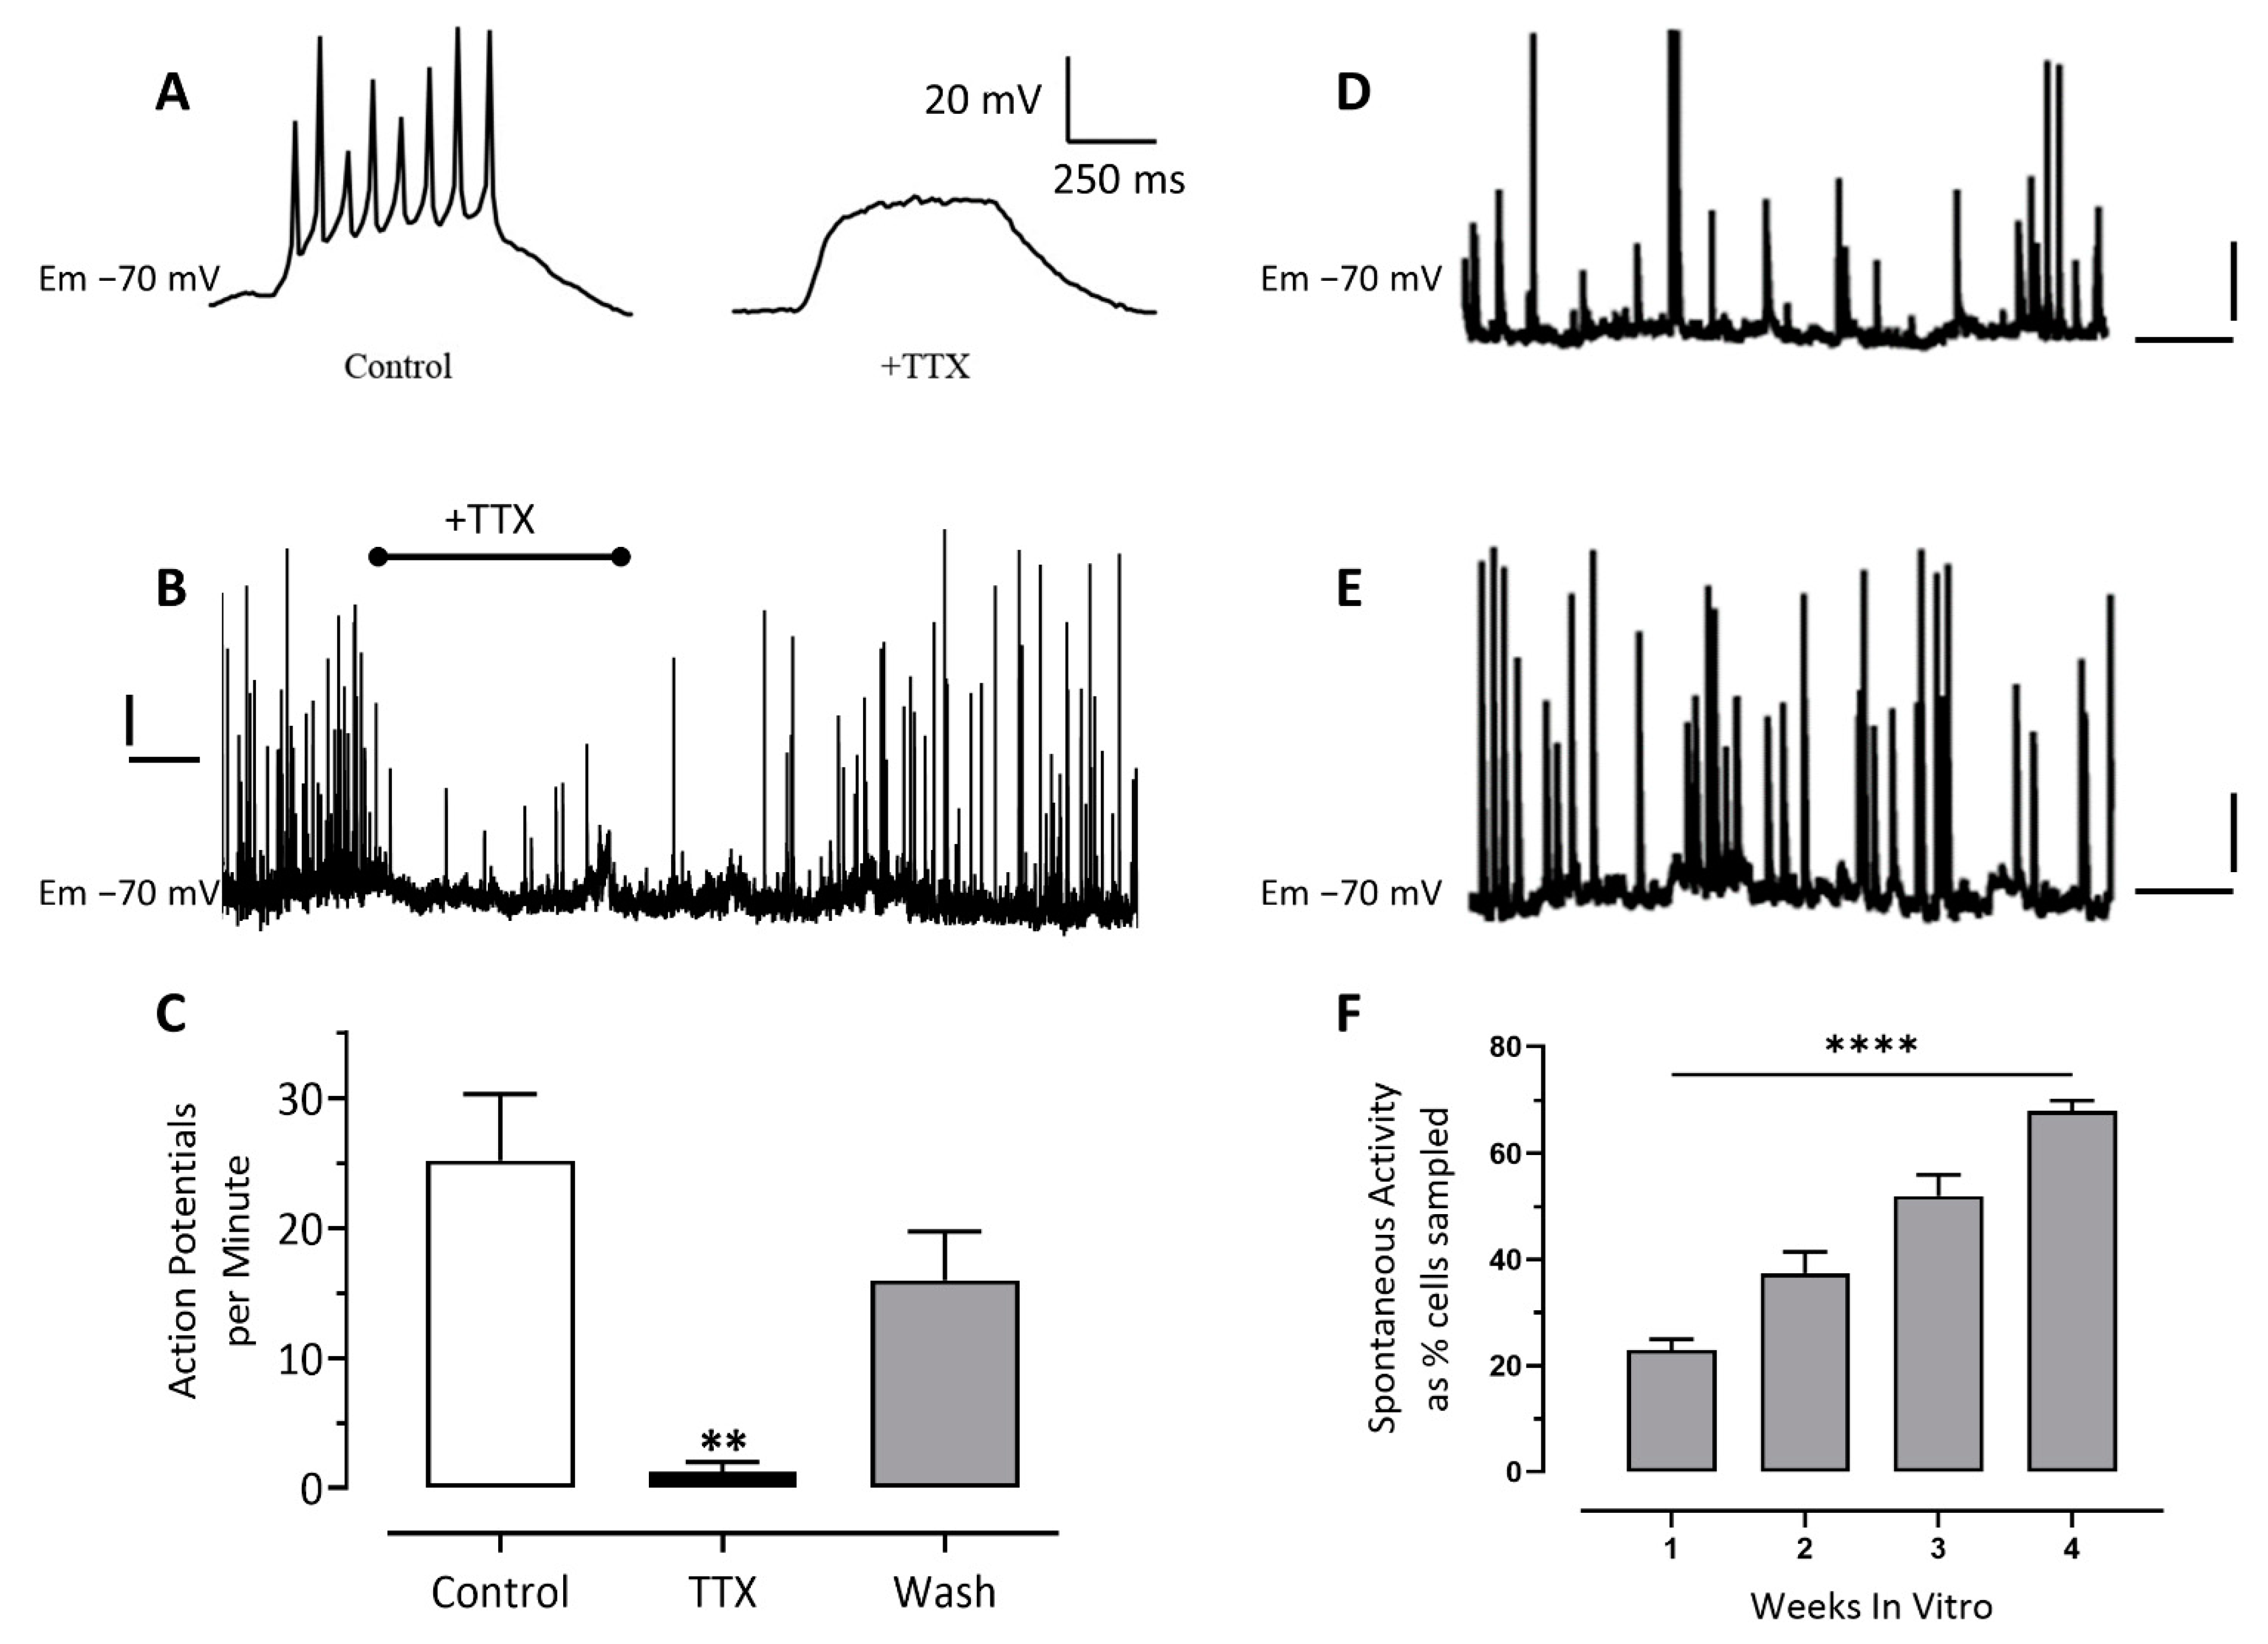

2.4. Patch-Clamp Electrophysiology

3.2. Patch-Clamp Electrophysiology